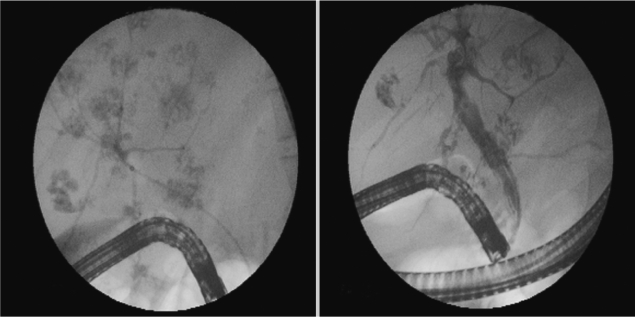

Parasite removal during ERCP is a therapeutic option in patients with acute obstructive cholangitis due to

F. gigantica [

11]. Triclabendazole at a single dose of 10 mg/kg is the chemotherapeutic regimen of choice against fascioliasis [

12]. The drug is active against both immature and adult parasites, with high cure rates. Our case had chronic and hepatobiliary phase of fascioliasis. ERCP findings of parasites was very interesting (such as foodprints of parasites) (

Fig. 1). We think this is a highly specific appearance for fascioliasis. The present

Fig. 1Endoscopic retrograde cholangiopancreatography (ERCP) findings of the patient, footprints of parasites.